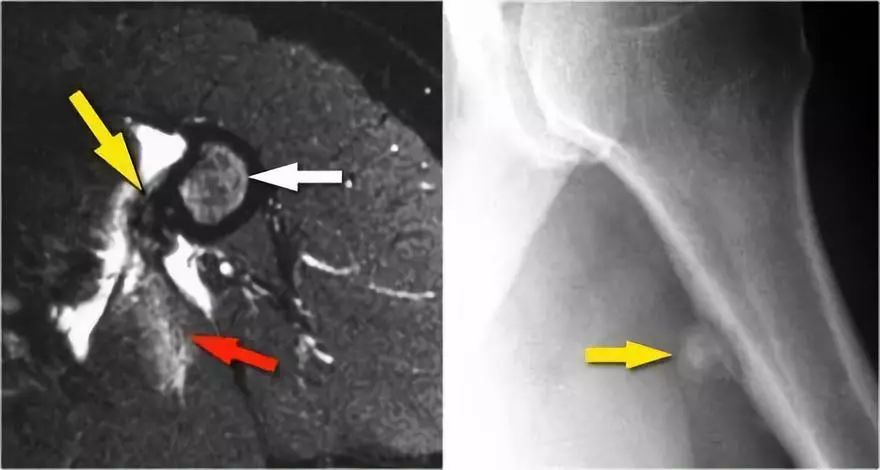

下面另一种慢性撕脱伤,被送到肿瘤外科医生,因为担心可能的近端皮质骨肉瘤。但是MR透露了以下内容:● 病变位于背阔肌肌腱插入肱骨(黄色箭头)。● 骨髓有一点点高信号,但看起来不那么异常。● 肌肉也受伤(红色箭头)。● 慢性撕脱伤在青少年中很常见,但在老年患者中也可见。● 问题是他们可能模仿感染或肿瘤。